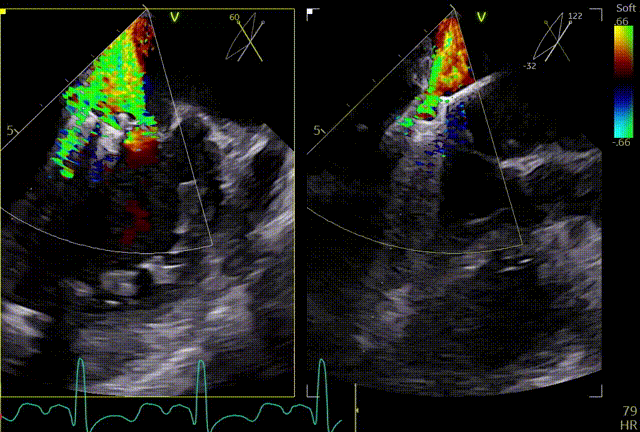

术前TEE及左房压

1区带彩

2区带彩

3区带彩